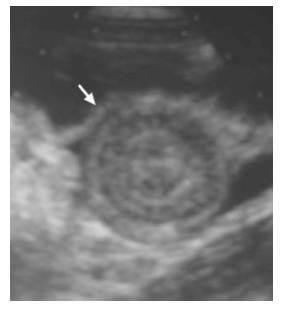

Uma criança de 9 meses de vida é levada ao pronto atendimento em razão de quadro de dor abdominal e fezes misturadas com sangue. Ao exame físico, nota-se massa abdominal palpável. É realizada ultrassonografia abdominal, representada na imagem. A criança apresenta FC= 110 bpm, FR = 25 irpm e saturação de oxigênio = 98% (ar ambiente).

Acerca desse caso clínico e dos conhecimentos médicos correlatos, julgue os itens a seguir.

Essa doença é causa incomum de abdome agudo em crianças.